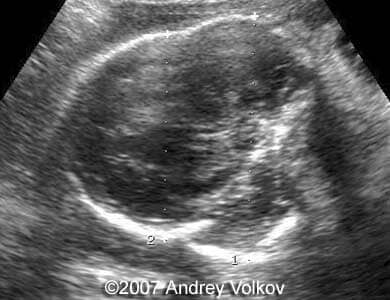

A 26-year old G1P0 from a nonconsanguineous couple (husband 35 years old), with noncontributive history, presented to our unit at 30 weeks of pregnancy. Our ultrasound examination revealed following findings:

• Cloverleaf shaped skull;

Images 1, 2: 30 weeks of pregnancy; Image 1 shows cloverleaf shaped fetal skull. Image 2 shows transverse scan through the fetal skull with lobar holoprosencephaly.